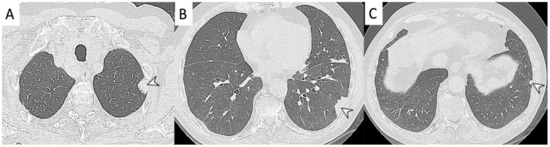

2.3. Microscopic Polyangiitis (MPA)

2.4. Granulomatosis with Polyangiitis (GPA-Wegener’s Disease)

2.5. Eosinophilic Granulomatosis with Polyangiitis (EGPA-Churg-Strauss)

| Vasculitis | HRCT Features |

|---|---|

| MPA | GGOs due to hemorrhagic alveolitis (common); consolidation, nodules with centrilobular distribution (less common) |

| GPA | Solid nodules, GGOs due to hemorrhagic alveolitis (common); halo sign, crazy paving (less common) |

| EGPA | Migrant GGOs, transient consolidation, irregular bronchial wall thickening, small nodules with peribronchial and centrilobular distribution, pleural effusion. |